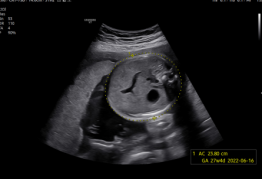

Exquisita calidad de imagen para una mayor fiabilidad y confianza

Mejore su apreciación sobre la evaluación del problema basado en un rendimiento de imagen excepcional impulsado por el motor de imagen principal de Samsung, Crystal Architecture™. El motor de imagen premium combina las ventajas del procesamiento de imágenes 2D mejorado y la expresión detallada del procesamiento de la señal de color. El V7 proporcionará una calidad de imagen sobresaliente para un diagnóstico de confianza.